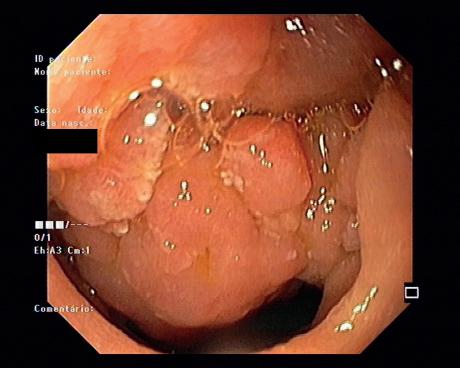

Figura 10.2.6 – ADC: A – Imagem de enteroscopia por cápsula a revelar formação globosa, congestiva, ulcerada e friável no jejuno proximal; B e C – BAE, que permitiu o esclarecimento etiológico e a realização de biópsias.